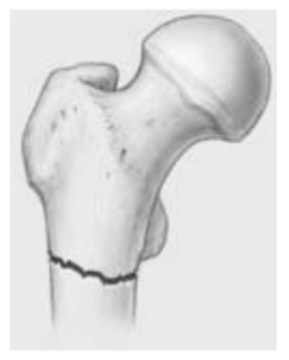

Quel type de fx de la hanche suis-je?

A

Intertrochantérienne

Vascularisation épargnée, pas de nécrose avasculaire 😎